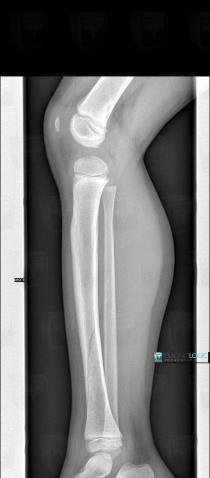

Fracture, Tibia - Mid part, X rays

Here is the specific information in the key image above:

- Diagnosis Fracture, Location(s) Tibia - Mid part, with gamuts